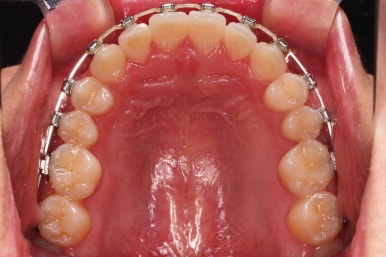

초진 시 입안의 모습이에요.

입을 벌리거나 말할 때는 앞니가 삐뚤고 덧니가 있어 미적으로 좋지 못하네요.

위아랫니가 모두 삐뚤어요.

특히 앞니가 삐뚤고 위아래 앞니가 고르게 덮여있는게 아니라 뒤죽박죽 엉켜있어서 치아의 마모도 굉장히 많이 되어있는 상태였어요.

이번 환자분은 치아가 삐뚤어 있는 양 + 돌출감을 고려했을 때 비발치로 가능할 것이라고 판단이 되었어요.